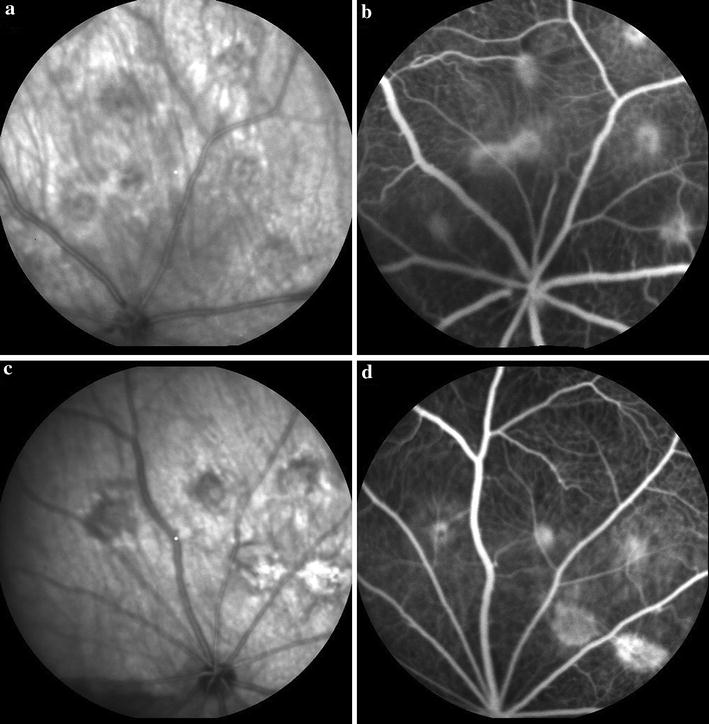

摘要:背景:进行了两阶段实验研究,确定玻璃体腔内注射伊马替尼(IVI)的最大安全剂量及其对大鼠脉络膜新生血管(CNV)的抑制作用。方法:在第一阶段,60只大鼠随机分为六组(A到F);其中五组接受伊马替尼(IVI)的浓度分别为 330 (A), 250 (B), 165 (C), 80 (D), 和40 (E) ug/5 ul, 对照组(F)接受平衡盐溶液(BSS)。除了视网膜电图(ERG),也进行常规病理分析和胶质纤维酸性蛋白免疫组化。在第二阶段,25只大鼠通过激光光凝诱导CNV,并分为两组。一组玻璃体腔内注射第一阶段摸索的IVI的最大安全剂量,另一组玻璃体腔内接受BSS注射。4周后,比较各组荧光素眼底血管造影荧光素渗漏的平均分和组织切片的平均CNV区数。结果:在第一阶段,ERG和组织病理学检查结果显示视网膜毒性组分别为A至D和A至C;因此,剂量为40 ug / 5uL的伊马替尼被指定为第二阶段的最大安全剂量。在第二阶段,伊马替尼治疗和对照组的眼睛晚期荧光素渗漏和CNV区域之间没有显著差异(分别,P = 0.62和P = 0.5)。结论:虽然有40ug/ 5uL IVI的安全剂量对CNV无抑制作用。需要进一步研究伊马替尼与常规抗CNV药物的可能协同作用。关键词:伊马替尼 脉络膜新生血管 血小板衍生生长因子 大鼠 荧光素血管造影术; 背景:年龄相关性黄斑变性(AMD)是导致65岁以上患者失明的主要原因,也是西方世界最常见的致盲原因。约10%的AMD患者表现为新生血管性疾病。研究表明,血管内皮生长因子(VEGF)是生理和病理血管生成的最重要的细胞因子,从而导致脉络膜新生血管(CNV)的形成。因此,目前抗VEGF药物是抗血管生成治疗的中流砥柱。血小板衍生生长因子(PDGF)是参与血管生成的第二种重要细胞因子,促进和招募细胞及平滑肌细胞,对血管的成熟和稳定必不可少。PDGF家族结合两种不同的受体,称为PDGF受体α和β。PDGF受体(PDGFR)是酪氨酸激酶受体,内皮细胞和血管平滑肌细胞中能表达更广泛的PDGFR-β。酪氨酸激酶是重要的细胞信号蛋白。多酪氨酸激酶参与血管生成,包括受体酪氨酸激酶,如血管内皮生长因子和PDGF受体。受体酪氨酸激酶对于细胞外信号转导到细胞内是必不可少的。一些受体酪氨酸激酶抑制剂如索拉非尼,西地尼布,舒尼替尼、帕唑帕尼最近被批准,这些药物,通过抑制血管内皮生长因子和PDGF信号,有望成为治疗CNV的新疗法。伊马替尼是一种酪氨酸激酶的特异性抑制剂,在2001被批准用于治疗人类癌症。它能抑制PDGFR信号转导。在PDGFR缺失的情况下,血管周细胞剥离、血管壁的完整性受到损害。这些血管对血管内皮生长因子的提取更加敏感,因此血管的回归更加突出。假设伊马替尼抑制或至少减慢CNV的进展,本研究的设计分为两个阶段。在第一阶段中,在大鼠模型中确定玻璃体内伊马替尼的最大安全剂量,并在第二阶段中,观察玻璃体腔内注射伊马替尼对激光诱导CNV大鼠模型可能的抑制作用。方法:动物: I期的研究的目的是确定玻璃体腔内伊马替尼(IVI)的最大安全剂量和II期其可能的CNV动物模型抑制作用。85只大鼠,体重200-300g。动物被饲养在一个塑料笼内,12 / 12小时黑-光周期下,自由采食和饮水。遵守视觉与眼科研究协会(ARVO)指南。所有操作过程,动物肌肉注射氯胺酮(80mg/kg)和盐酸甲苯噻嗪(5 mg/kg)麻醉。一滴0.5%托吡卡胺扩张瞳孔。最后在I期和II期分别进行ERG和荧光素眼底血管造影后,在深度麻醉情况下,颈椎脱臼处死大鼠。玻璃体腔内伊马替尼注射准备:目前,伊马替尼仅有100和400毫克片剂,并没有任何注射剂。药物的活性物质是甲磺酸伊马替尼,这是一种白色的苯基氨基嘧啶衍生物微黄色结晶粉末耐光。甲磺酸伊马替尼在水溶液中的溶解度取决于pH值,在pH为5.5 - 5.8获得其最高溶解度。用微量硫酸调定无菌蒸馏水pH 5.5 - 5.8。然而,添加伊马替尼粉末后,最终溶液的pH值为中性。将40、80、165,250和330毫克的纯粉放入5毫升容量瓶中,用蒸馏水溶解,然后作量制备40,80,165,250和330 ug / 5uL浓度注射剂。第一阶段:六十只大鼠随机分为六组(A到F);其中五组右眼注射IVI浓度分别为330(A)、250(B)、165(C)、80(D),和40(E)ug/ 5ul,对照组(F)注射平衡盐溶液(BSS)。注射是在无菌条件下进行,使用手术显微镜操作。对实验前基线,注射后1周和4周进行视网膜电图(ERG)检查。4周后,处死大鼠,其右眼被摘除进行组织病理学分析。在ERG和组织病理学结果的基础上,确定IVI II期的最大安全剂量。视网膜电图:在伊马替尼注射前、注射后1周和4周,进行视网膜电图。所有程序都在黑暗中进行,红外线照明和图像转换器。ERG操作如前面描述。简而言之,至少2小时的暗适应后,动物麻醉后散瞳。麻醉期间体温维持在36°C和37°C之间。然后将动物置于有温度控制加热垫的记录室中。放置角膜金线电极,记录ERG信号。用RETI-port /扫描21电生理诊断系统记录采集ERG信号。同时进行双眼明视、暗视反应。ERG b波振幅变化低于基线值至少30%认为是明显的。比较各组和组之间ERG在不同时间点的结果。组织病理学和免疫组化检查:ERG记录后,将动物处死,摘除眼球10%福尔马林固定,切片进行光镜检查。每只眼睛轴向分割进行石蜡包埋。5?M组织切片经HE染色后光镜下由两个眼科病理学家观察视网膜各层的完整性和视网膜出血,出现是炎症和萎缩。此外,也进行了神经胶质纤维酸性蛋白(GFAP)的免疫组化研究。与对照组相比,治疗组视网膜苗Muller细胞GFAP免疫反应性明显增加。组织病理学表明视网膜毒性变化包括:视网膜层的完整性的情况下,视网膜出血的存在,和/或炎症、视网膜神经胶质增生或萎缩的存在和存在显著GFAP免疫反应。第二阶段:25只大鼠右眼诱导实验性CNV。动物随机分为治疗组(14只)接受第一阶段确定的IVI最大安全剂量和对照组(11只)接受玻璃体腔注射BSS。4周后,动物进行荧光素眼底血管造影(FAG),然后被安乐死。通过组织病理学检查评估CNV区域。激光诱导脉络膜新生血管:我们用色素大鼠作为激光诱导的CNV模型,因为大鼠视网膜同人类视网膜非常相似,均匀着色,光凝后表现出较高的CNV。大鼠麻醉后,扩张他们的瞳孔。通过使用裂隙灯红外二极管激光传输系统和非接触式78 D透镜,在每个眼睛的主要血管之间施加六个激光点。每一个激光点的蒸汽气泡的发展指向为Bruch膜破裂。荧光素眼底血管造影:激光光凝四周后,进行荧光素血管造影(FAG),来揭示CNV。在全身麻醉情况下进行血管造影,腹腔注射0.1毫升10%荧光素钠。图片由视网膜专家进行解释,对晚期强荧光血管造影存在病变分级为:0,无泄漏;1,轻微的泄漏;2,中度泄漏;3、突出的泄漏。对任何大鼠的病变的泄漏分数进行了总结,产生一个单一的值,每只大鼠分数为三个观察员的平均分数。组织切片中脉络膜新生血管面积的测量:福尔马林固定眼睛,如上所述,轴向一分为二进行组织病理学处理。石蜡包埋后,连续切片,苏木精-伊红染色,尝试连续切片整个CNV病变。光镜下进行切片检查。选择最大的CNV的部分并使用数码相机拍摄。图像转移到计算机和使用ImageJ软件计算CNV面积。结果:第一阶段:A、C、F组各一只,D组2只,E组3只动物没有存活,被实验排除。视网膜电图:表一显示注射IVI前、注射1周和4周后各研究组明视、暗视的ERG平均振幅。各组ERG图形几乎相同。组与组之间,每组在指定的时间点观察的ERG明视结果无显著差异。然而,注射IVI 4周后A组到D组暗视ERG的b波平均振幅明显减少。E和F组没有明显变化。光镜观察:组织病理学分析显示,视网膜坏死的改变是视网膜层完整性丧失和视网膜萎缩改变的结果。D组和E组的病理组织学特征、GFAP免疫反应同对照组相比无显著差异,考虑ERG及病理结果,40ug/ 5uLIVI为II期的最大安全剂量。第二阶段:25只大鼠中治疗组有3只对照组有1只大鼠被淘汰。荧光素眼底血管造影脉络膜新生血管评分:激光应用四周后,FAG显示激光烧伤部位CNV的发展。伊马替尼注射眼同对照组相比,CNV平均得分没有显着差异。组织切片中脉络膜新生血管区:IVI治疗组与对照组大鼠脉络膜新生血管生长较正常均无显著性差异。结论:玻璃体腔内伊马替尼最大安全剂量为40ug/ 5uL,在这项研究中,对模型大鼠CNV无抑制作用。然而,伊马替尼可能同常规抗VEGF治疗CNV药物有协同作用,这需要进一步调查。